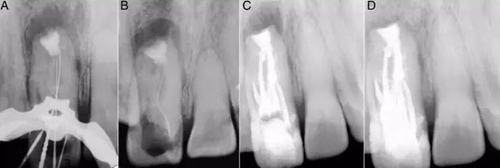

圖3:A:5個根管開口;B:DM根管傾斜走形,在MI頰側(cè);C和D:倒充填和MTA使用后的圖像。

復(fù)診在局部麻醉后翻開粘骨膜瓣,搔刮骨缺損,暴露根尖區(qū)。切除根尖2mm以消除根尖的薄弱邊緣。預(yù)備根尖5mm區(qū)域(3C),MTA倒充填(3D)。皮瓣復(fù)位后進(jìn)行間斷縫合,5天后拆除縫線。

兩周后患者無不適,進(jìn)行根管充填。由于根管間有很多的交通(5A),所以在治療過程中15#K銼陷入M和MI間的交通支中并和柄分離(5B)。使用超聲將分離器械取出后進(jìn)行徹底蕩洗,干燥后用熱牙膠充填系統(tǒng)進(jìn)行充填(5C)。一個月后,患者完全無癥狀,復(fù)合樹脂充填。在3,6,12月進(jìn)行了復(fù)查(5D)。

圖5:A:根管間有很多相互交通;B:進(jìn)入MI根管后分離的15號K挫;C:充填后的圖像;D:1年后的隨訪。